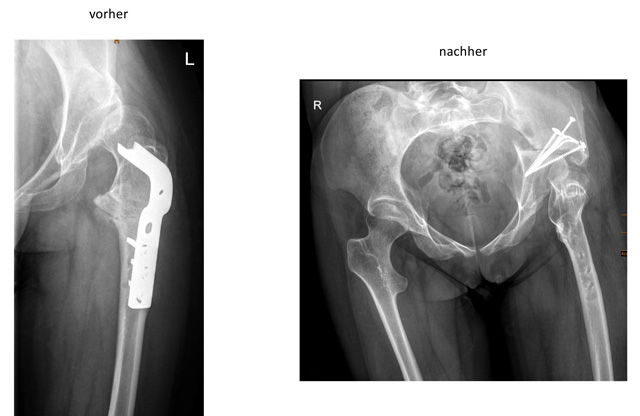

Bei der Operation wird der Beckenknochen in der Umgebung der Pfanne kontrolliert durchtrennt und die Pfanne dann neu orientiert und meist mit Schrauben wieder fixiert. Dadurch kann die Pfanne bezüglich Tiefe und Ausrichtung verändert werden.

Triple-Osteodomie